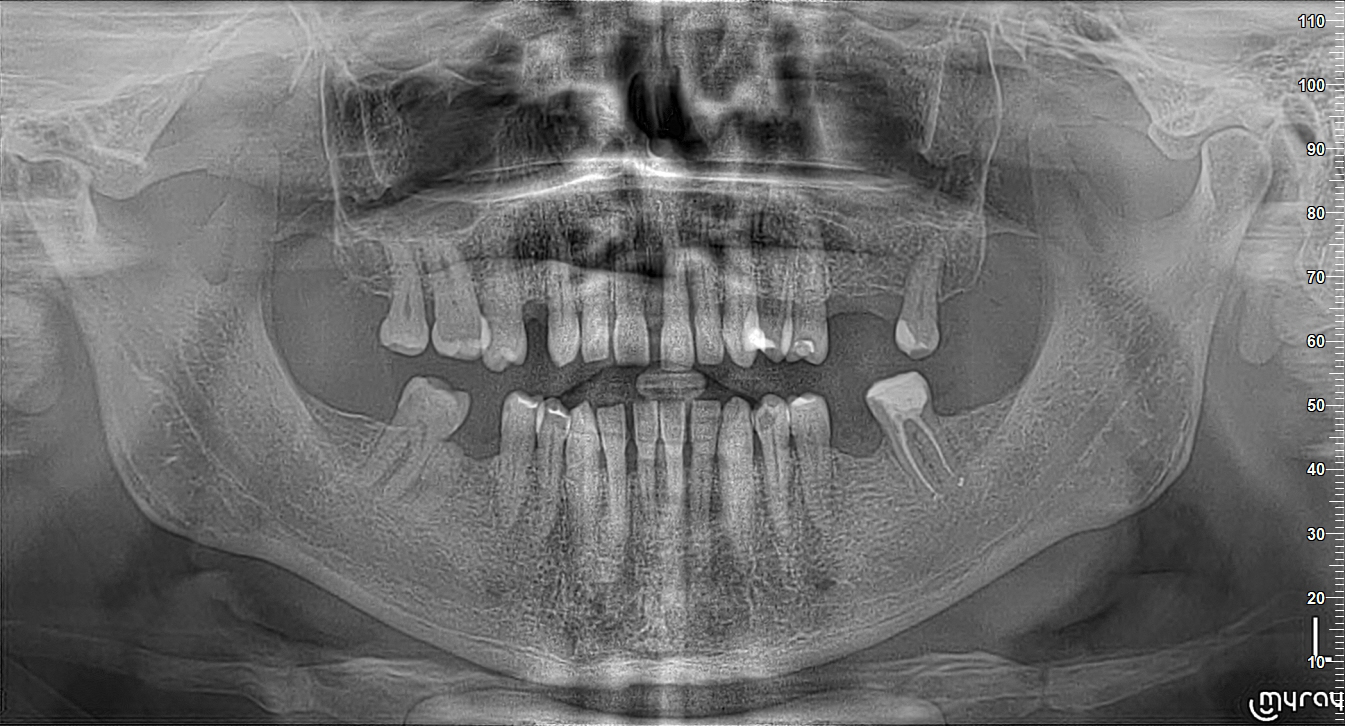

Patient InformationA patient presented with severe mobility of tooth 21.

Medical history revealed that the patient was a non-smoker, had no diabetes, and no relevant systemic conditions. Dental history indicated previous trauma to tooth 21. Clinical examination showed Grade III mobility of tooth 21, localized severe periodontal destruction around the tooth, chronic periodontitis, bleeding on probing (BoP) of 10%, and the presence of calculus in the lower jaw. CBCT examination demonstrated complete buccal bone dehiscence around tooth 21 with limited remaining bone support. Therefore, extraction of tooth 21 was indicated.